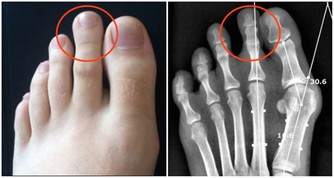

醫學認為,汗皰疹是濕疹的一種,是一種對稱性的、複發性的、多發生在手掌的水皰性疾病。汗皰疹發病有以下特點:

2、水皰為位於表皮深處的小水皰,米粒大小,半球形,略高於皮表,分散或成群發生在手上;

3、內含清澈漿液,發亮,偶爾可變渾濁;

4、小水泡多不自行破裂,破裂后可見圓領狀脫皮;

5、一般無瘙癢、疼痛等異常感覺。